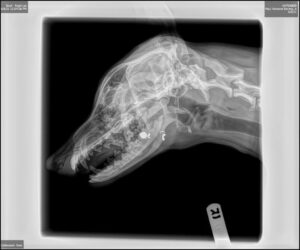

Kanada wrapped up the dog and brought it to Maui Humane Society, fearing the worst. Upon intake at the shelter, it was noted that the young female puppy had a circular hole in her temple was bleeding from body injuries consistent with road rash, and had a large open wound on her jaw.

On-call veterinarian Dr. Jennifer Fitzpatrick rushed to the shelter to assess the situation and provide the dog with pain medications, antibiotics and wound treatment. Her jaw was supported as x-rays were ordered.